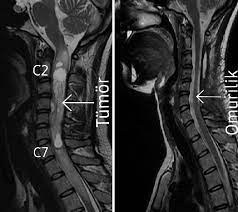

MR; omurganın primer tümörlerinin tanı ve değerlendirilmesinde tercih edilecek bir yöntemdir. Avantajları; yumuşak doku görüntülemesinin iyi olması, multiplanar görüntü elde edilebilmesi, nöral bası veya infiltrasyonun değerlendirilebilmesidir.